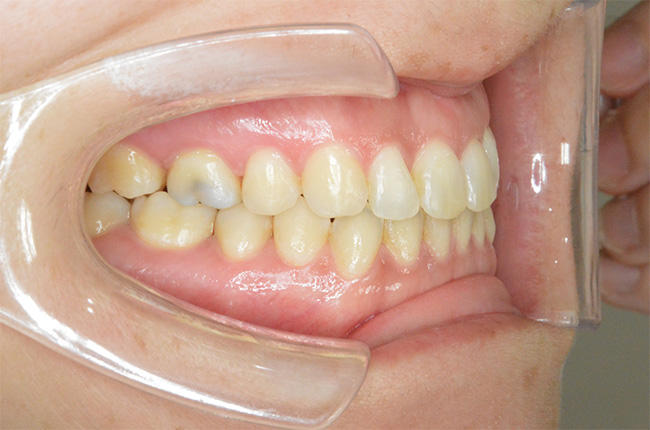

治療終了時

| 治療方法 | 上下顎小臼歯4本抜歯、ワイヤー矯正 |

| 治療内容 | 抜歯のスペースを使用して、上下前歯を後退させた |

| 治療期間 | 2年1ヵ月 |